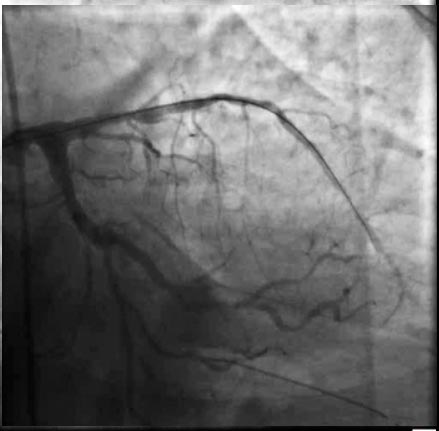

Ангиограмма показала нормальные коронарные артерии.